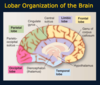

The surface of the brain consists of creases and folds, called ____ and _____ that are unique to every individual, much like fingerprints, but common features permit identification of important brain topography.

gyri and sulci

What separates the frontal lobe from the parietal lobe?

The central sulcus

What divides the temporal lobe from the frontal and parietal lobes? Lobes are large areas of the brain that house specific functions

Sylvian fissure

The frontal lobe contains many executive functions such as what?

deciding what you want to do next, what thoughts you want to express in words or writing, where you want to move your eyes to view the world, where you want place your arm, manipulate an object or move your leg. Think of it as a “to do” or the motor part of the brain.

What does the parietal lobe do?

The parietal lobe is the area that receives and interprets sensory information from principal modalities such as fine touch, position sense, vibration, pain and temperature. It determines the texture, shape, temperature and other characteristics that allow you to identify an object held in your hand but also to know where your hand is in three dimensional space.

Think of it as an area of the brain that interprets the physical environment around you.

What does the temporal lobe do?

The temporal lobe has several important functions. In the superior temporal gyrus lies the primary auditory cortex (called Heschl’s gyrus) that processes sounds. It is shown by the asterisk. Just posterior to it lies “Wernicke’s area” that interprets the processed sounds as words and mediates the comprehension of language.

Another important function of the temporal lobe is memory (part of the Limbic system)

What are the main roles of the occipital lobe?

it also interprets the environment but is devoted to a special sense: vision.

The cerebellum consists of two lobes or hemispheres, right and left. What do they do?

Unlike the cerebral hemispheres that govern the contralateral side of the body and sensory world, the cerebellar hemispheres receive and organize motor information about the limbs on the same or ipsilateral side of the body. Their function is to smooth out anticipated movements so movements are coordinated with what the rest of the body is doing.

The medial view of the brain shows the four major subdivisions of the cerebral hemispheres, the frontal, parietal, temporal, and occipital lobes, plus the limbic lobe that contains elements of the limbic system. What does the limbic system do?

It is involved in emotion, learning and in the formation of new memories. (older memories are ok)

There is no obvious boundary between the parietal and occipital lobes on the lateral view of the hemisphere but in the medial view, the ______ clearly demarcates the two lobes.

parieto-occipital sulcus

This slide shows the major lobes of the brain from a lateral, medial, superior and inferior (base of the brain) views. Note the interhemispheric fissure. This is the other major fissure in addition to the lateral or Sylvian fissure.